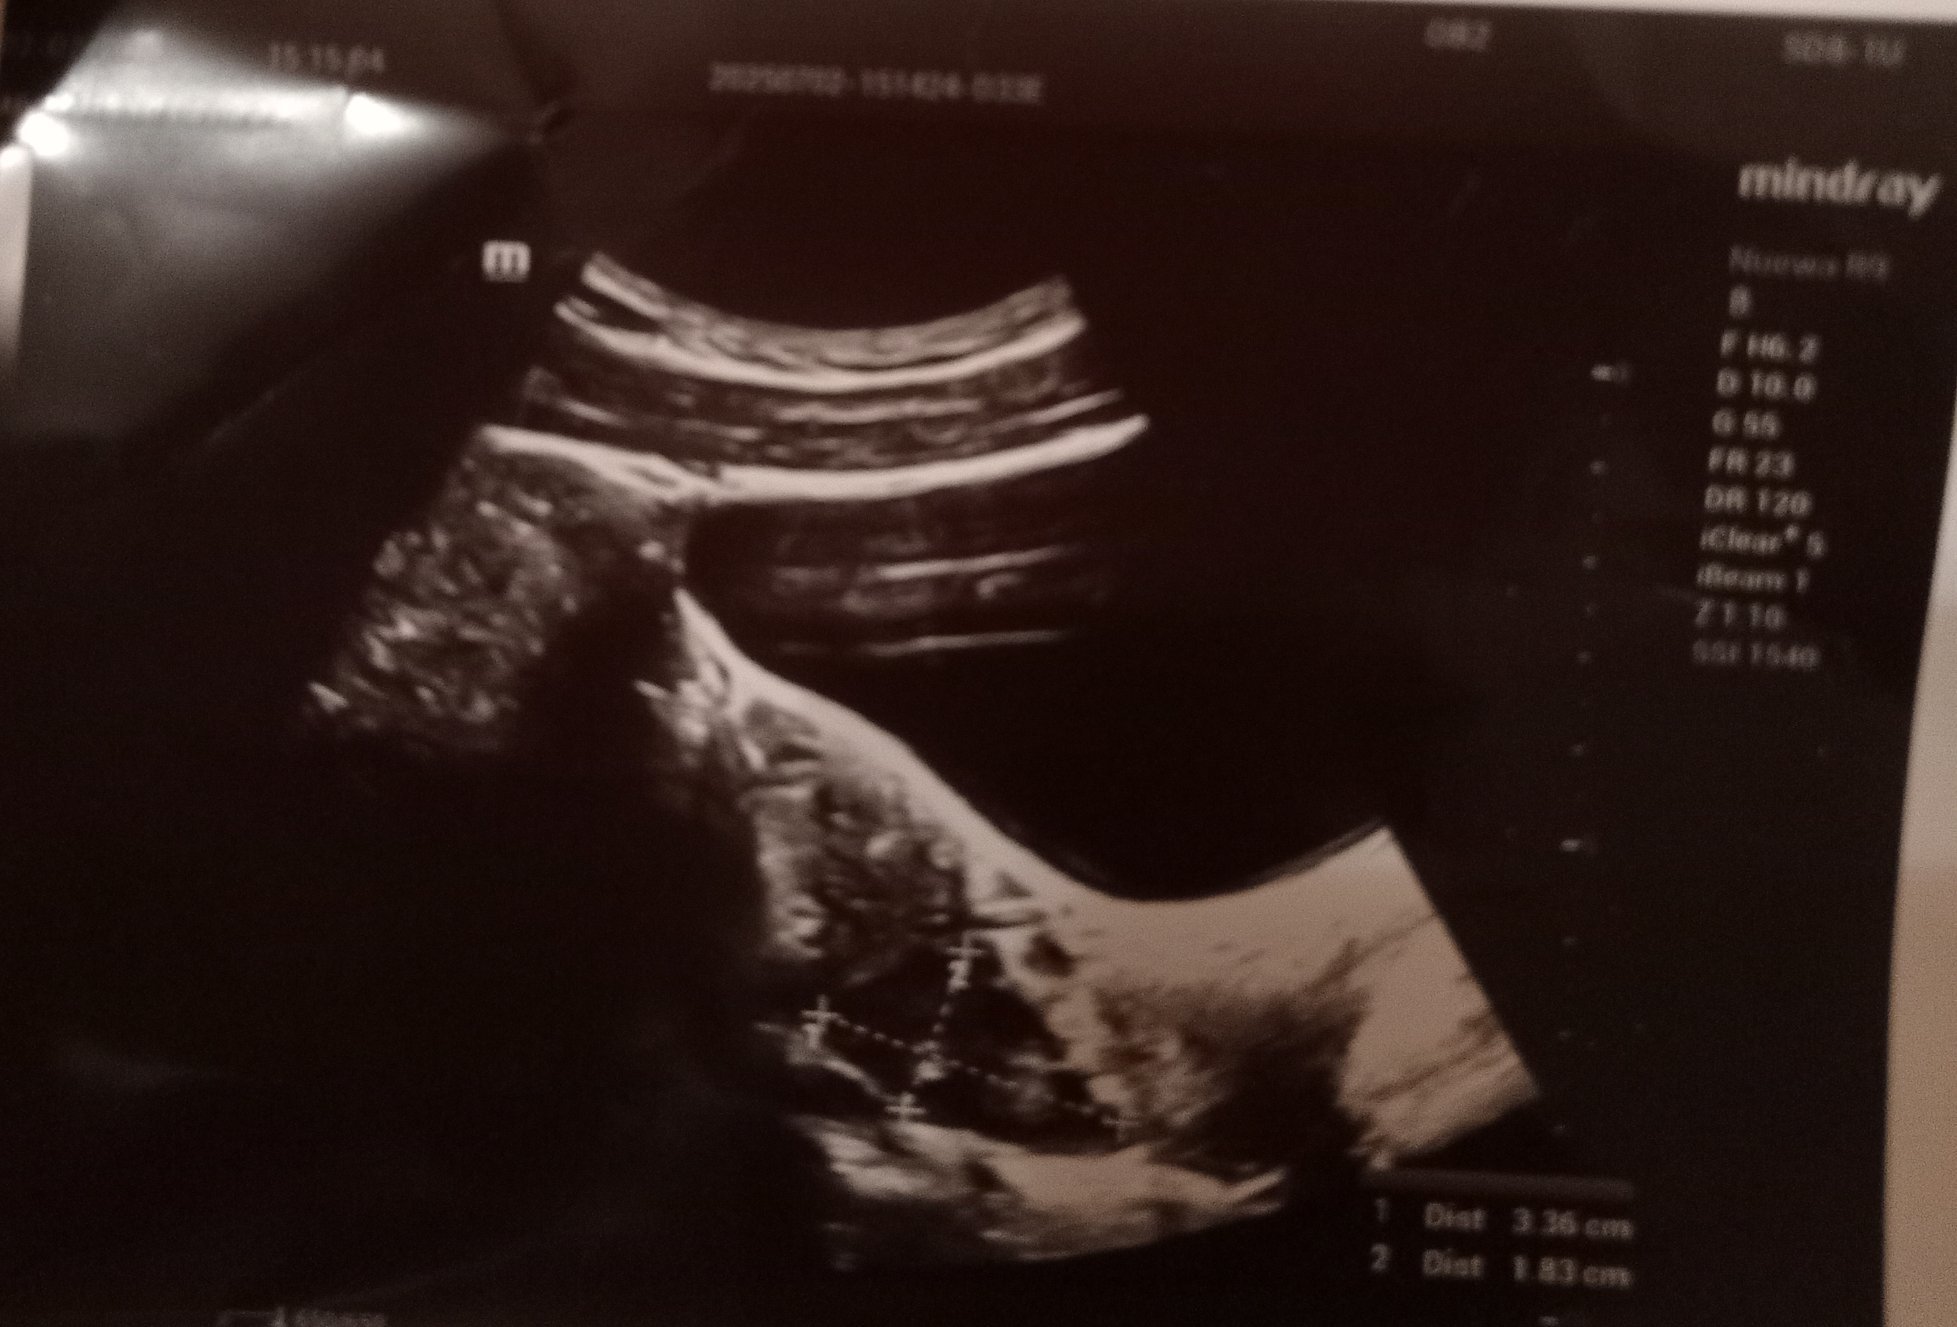

Ето и снимките от ехографа, какво мислите?

Скрит текст:

.